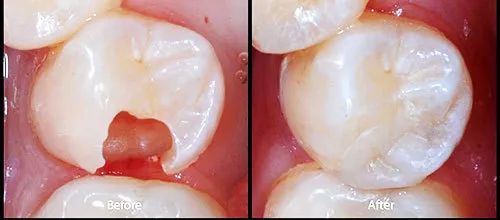

如果银汞合金已经损坏或者又有继发龋坏,这样是需要替换的。像这样的↓

如果银汞合金完好,也没有继发龋坏,功能上讲,是没必要替换的。如果是为了好看,那就需要自己权衡了。有一些国家已经禁用银汞合金,主要是汞污染环境和潜在的不安全因素。